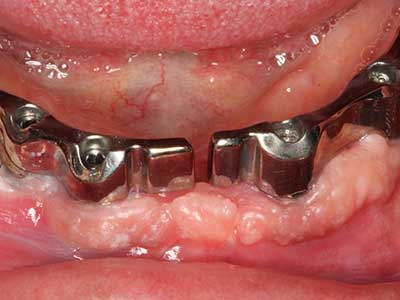

Abb. 27: 21-jähriger Patient nach Umstellungsosteotomie mit persistierender Retrognathie bei Klasse II-Dysgnathie.

Abb. 28: Im Rahmen der Metallentfernung erfolgt die Abtrennung der basalen Kinnanteile unter Beibehaltung der lingualen Blutversorgung mit dem Piezomed.

Abb. 29: Vorverlagerung des Kinns um 5 mm und Fixierung mittels zweier Osteosyntheseplatten (KLS Martin). Im Randbereich sind beide Nn. mentalii zu erkennen.